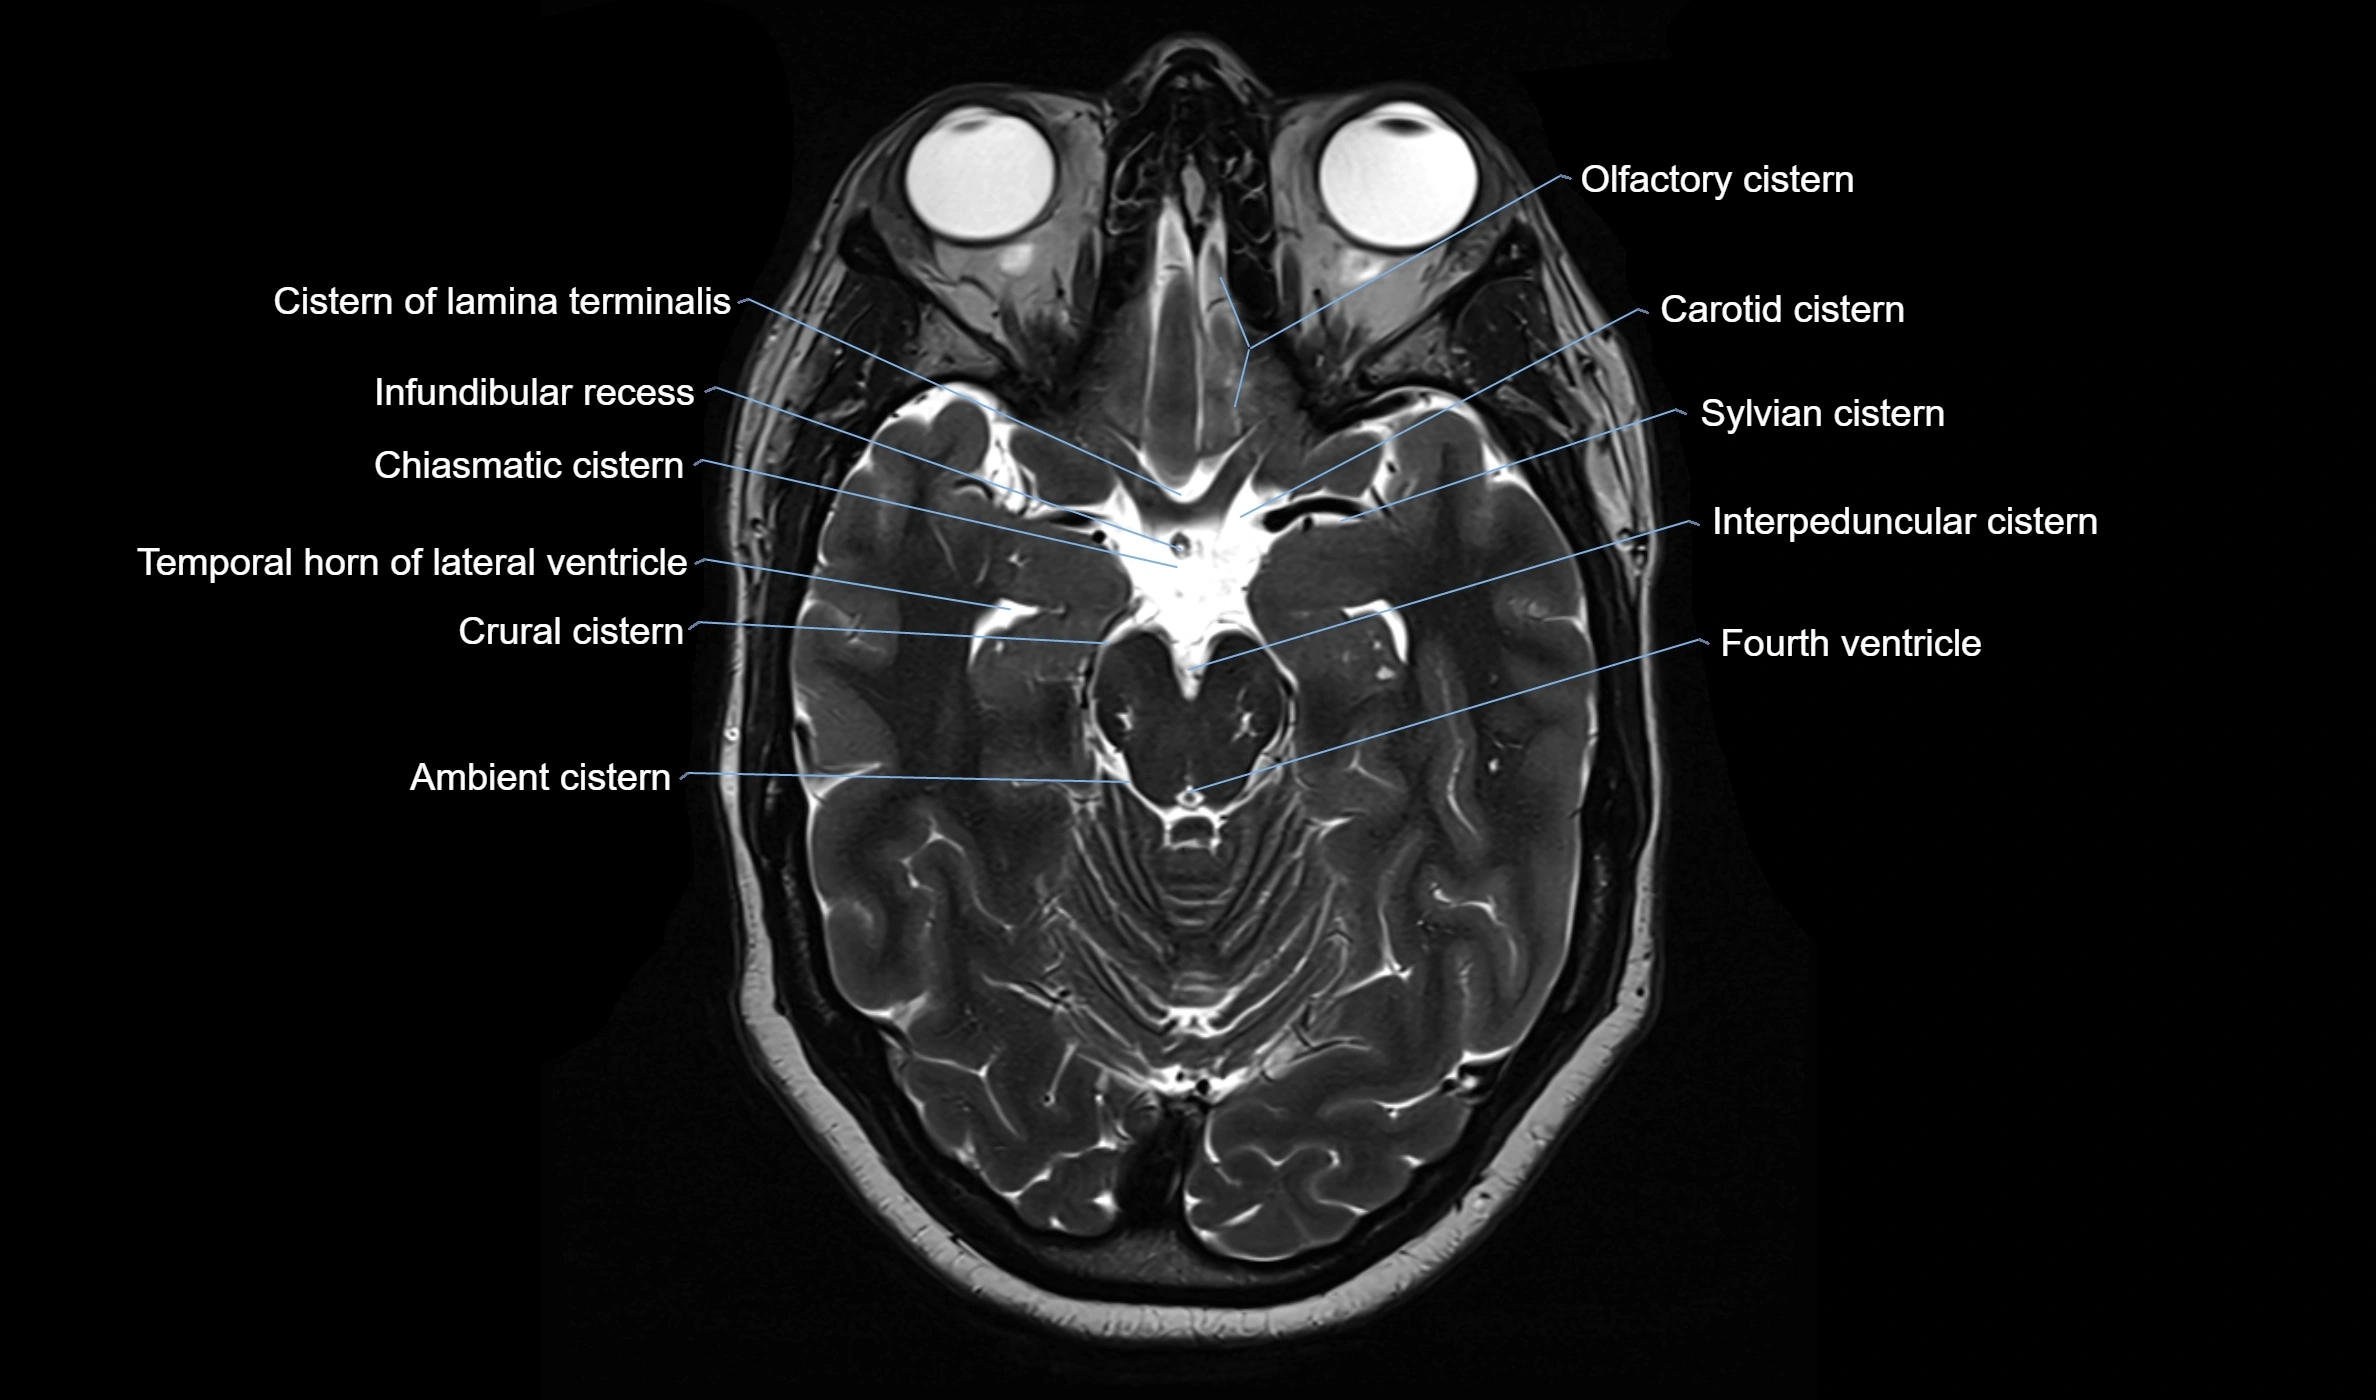

MRI images

image